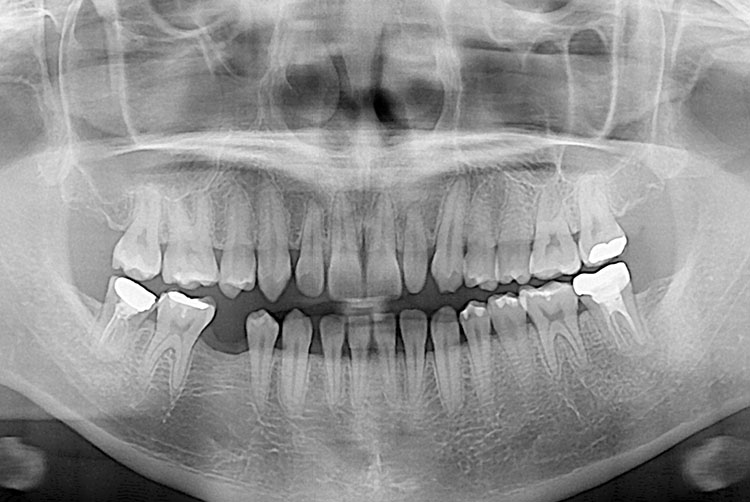

[임플란트] 임플란트

PX20190528_161221_0939_00000000.jpg

치료후 : 2019-05-28

세종치과는 많은 환자와 다양한 케이스를 바탕으로 항상 편안한 임플란트 수술을 제공하고자 노력하고,

오래동안 튼튼히 쓸 수 있는 임플란트 수술을 가장 큰 목표로 삼고 있습니다.